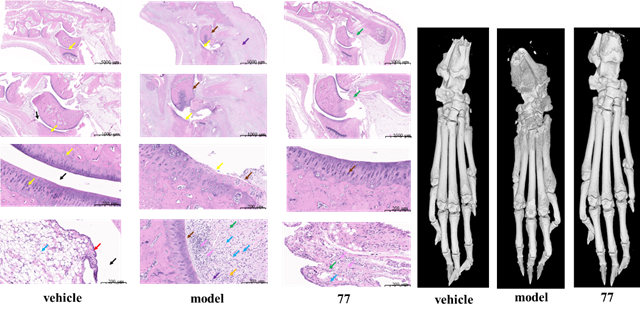

近日,北京理工大學化學與化工學院醫藥分子科學與制劑工程工信部重點實驗室梁建華課題組,以天然產物二苯乙烯為先導物,基于骨架躍遷策略成功優選出一種“新型可溶性環氧水解酶”(sEH)抑制劑DJ-89(化合物77),為臨床需求未滿足的胰腺炎和關節炎的治療帶來新策略,2025年4月14日以“Discovery of Phenylacylpiperidine as Novel sEH Inhibitors through Scaffold Hopping of Natural Stilbene”為題在線發表在國際權威的新藥研發期刊《 Journal of Medicinal Chemistry 》(文章鏈接:https://doi.org/10.1021/acs.jmedchem.5c00685)。該候選藥物的體外sEH酶抑制活性(IC50低至0.51 nM)遠高于現有臨床候選藥物EC5026;并在急性和慢性炎癥動物模型中抗炎鎮痛藥效顯著。在風濕性關節炎模型中DJ-89通過抑制肝臟中sEH酶活性,提高抗炎因子EET水平,有效減輕組織和關節的炎癥癥狀,顯著改善了動物的健康狀況。與現有關節炎臨床藥物治療方法相比,DJ-89具有新的作用靶標和生物途徑,具有優異的臨床安全性,這一研究成果為風濕性關節炎等自身免疫性疾病的治療提供了全新的解決方案。

風濕性關節炎等慢性炎癥性疾病因高致殘率和現有藥物副作用大、療效不穩定等問題,而胰腺炎目前臨床沒有有效藥物,長期面臨治療困境。sEH在炎癥調控中至關重要,它代謝體內的有益的抗炎因子—環氧二十碳三烯酸,促使炎癥發展,成為抗炎藥物研發熱門靶點。不過,此前進入臨床II期試驗的sEH抑制劑,因藥代動力學缺陷或安全性問題折戟,目前沒有任何藥物被批準上市。這一現狀使得開發具有全新化學骨架的藥物變得尤為迫切,也極具重要意義。此前,我們設計了多種骨架的sEH抑制劑( European Journal of Medicinal Chemistry 2024, 266, 116113; European Journal of Medicinal Chemistry 2024, 280.; Journal of Medicinal Chemistry 2024, 67, 18412?18447; Journal of Medicinal Chemistry 2024, 67, 22168-22190.)。此次,我們基于“骨架躍遷”策略,從天然二苯乙烯衍生物出發,設計合成了九種新型骨架化合物,最終篩選出以“苯乙酰哌啶”為核心骨架的DJ-89。該藥物在多項實驗中表現出色:1)超強抑制活性:DJ-89對sEH的抑制活性(IC50 = 0.51 nM)比臨床候選藥EC5026(19 nM)和TPPU(44 nM)高數十倍。2)獨特抗炎機制:通過提升EETs水平并降低其代謝產物DHETs,DJ-89顯著抑制促炎因子(TNF-α、IL-1β)水平,同時增加抗炎因子IL-10水平,這一“雙效調節”機制具有創新性。3)體內顯著療效:在類風濕性關節炎大鼠模型中,DJ-89(10 mg/kg口服)有效減輕關節腫脹和骨侵蝕;在急性胰腺炎模型中,其抑制胰腺組織的炎癥細胞浸潤效果突出,同時血漿IL-6水平下降50%。4)優異的安全性:對hERG和CYP酶影響微弱,大幅降低臨床用藥風險。5)藥代動力學良好:口服生物利用度達8.3%,半衰期1.89小時,且主要富集于sEH表達量高的肝、腎部位,腦部暴露量低,預示其全身抗炎作用顯著且中樞副作用風險小。